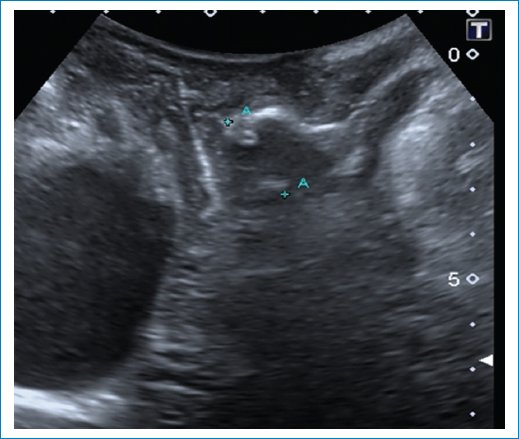

Compartimento posterior6

• – Rectocele con defecto de tabique rectovaginal (Fig. 15).

• – Prolapso con tabique rectovaginal intacto-hipermovilidad perineal.

Figura 15. Se observa un rectocele anterior durante Valsalva.